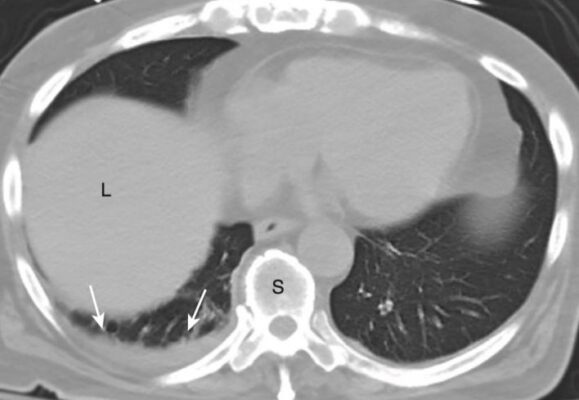

- Khi nửa ngực của một người trưởng thành chứa khoảng 2 L chất dịch, toàn bộ nửa ngực sẽ bị mờ (Hình 11).

- Khi chất dịch đầy khoang màng phổi, phổi có xu hướng bị xẹp thụ động (xẹp phổi).

- Trên phim chụp X quang phổi thông thường, các tràn dịch lớn tạo hình ảnh mờ đủ mức bao bọc và che khuất bệnh lý bên dưới ở phổi. CT là phương thức thường được sử dụng để đánh giá phổi bên dưới khi có tràn dịch lớn (Hình 12).

- Tràn dịch lượng lớn có thể hoạt động như một khối và làm dịch chuyển tim và khí quản ra xa bên bị mờ.